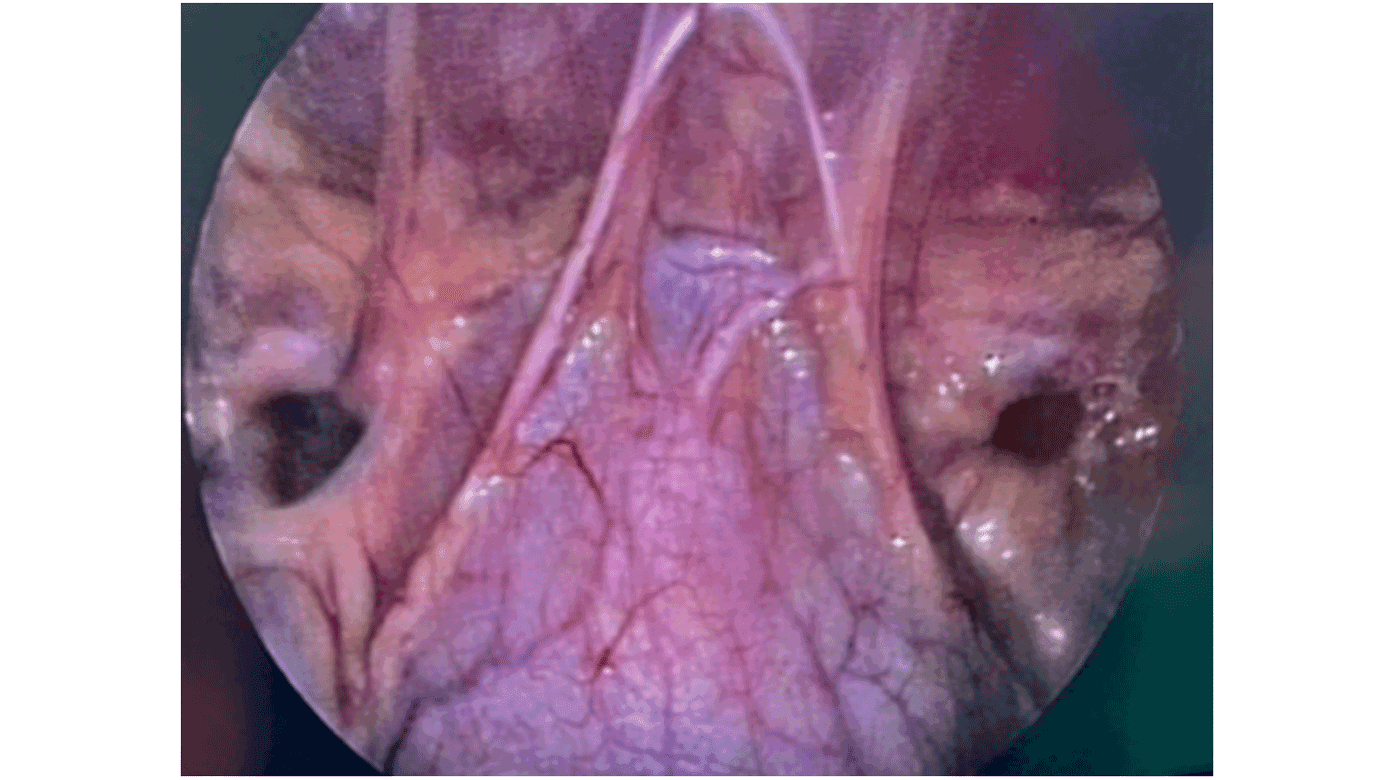

Da patienten som femårig blev genhenvist med samme anamnese og kliniske fund, blev der på ny foretaget en eksploration af højre lyske i generel anæstesi, igen uden fund af ingvinalhernie. Der var dog fortsat klinisk og anamnestisk mistanke om ingvinalhernie. Forældrene kunne fremvise et billede med en frembuling i højre lyske under ligamentum inguinale, hvorfor det blev besluttet at udføre en diagnostisk laparoskopi. Fundet ved denne operation var uventet: bilateralt femoralhernie (Figur 1). Ligesom ved en typisk laparoskopisk operation for femoralhernie blev peritoneum over brokdefekterne løsnet, og broksække med præperitoneale lipomer blev reponeret på begge sider. Brokdefekterne blev lukket med selvfikserende, langsomt resorberbare suturer. Der blev ikke anlagt mèche, men man foretog plicering og fiksering af broksækkene for at styrke abdominalvæggen i lyskeregionen på begge sider. Patienten blev udskrevet velbefindende den efterfølgende dag.